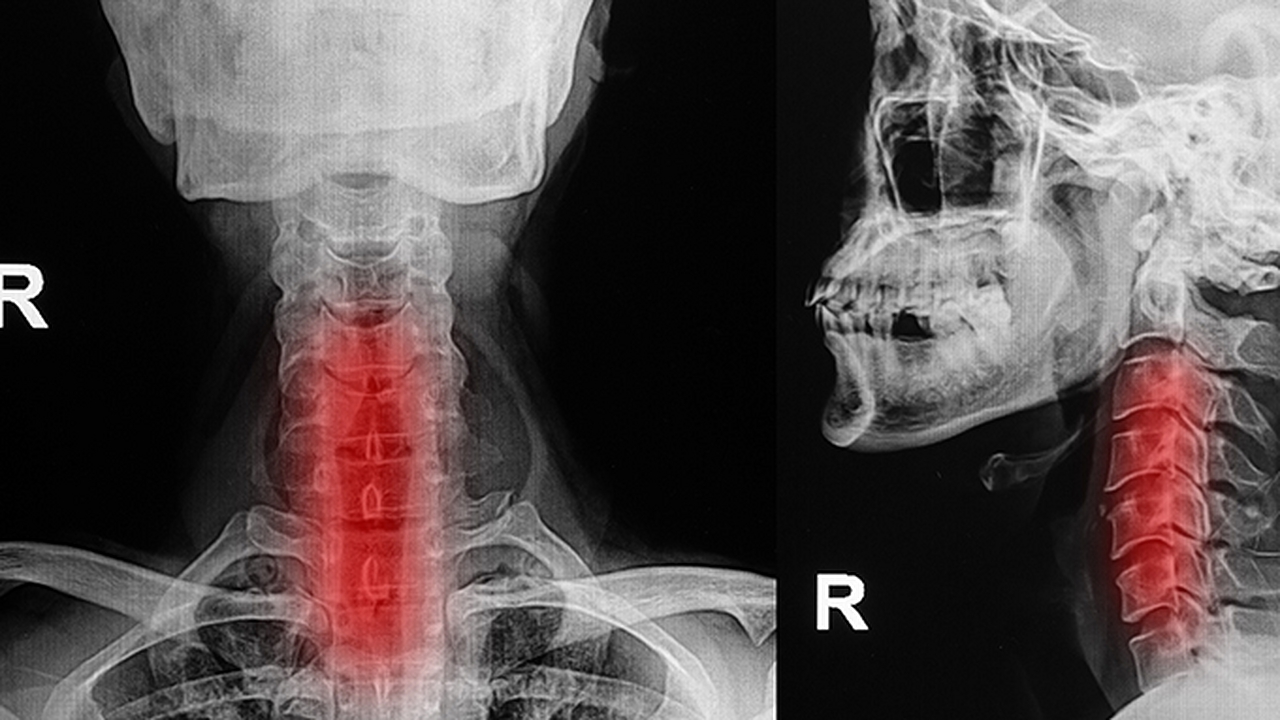

持續(xù)腫脹超過兩周建議進(jìn)行喉鏡排查聲帶病變,抽血檢查甲狀腺功能五項(xiàng)。過敏體質(zhì)者需做血清IgE檢測(cè)明確過敏原。若伴隨吞咽困難或呼吸不暢需立即就診,排除會(huì)厭炎等急癥。